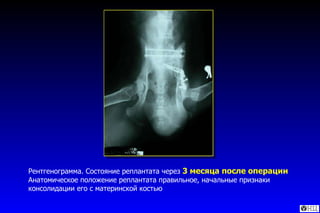

Рентгенограмма. Состояние реплантата через  3 месяца после операции  Анатомическое положение реплантата правильное, начальные признаки консолидации его с материнской костью

Рентгенограмма. Состояние реплантатачерез 3 месяца после операции Анатомическое положение реплантата правильное, начальные признаки консолидации его с материнской костью